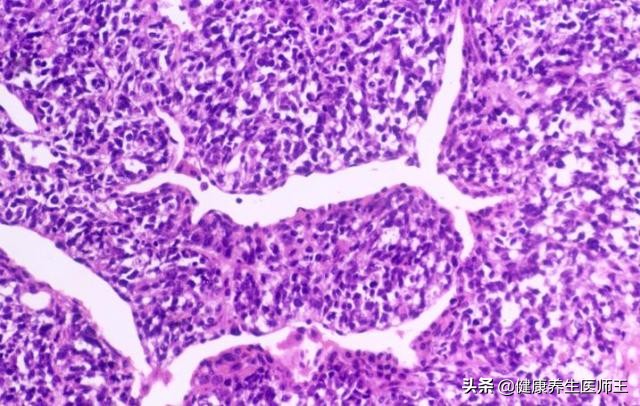

CK19主要分布于单、复层上皮细胞内。免疫组化研究表明, 覆盖正常支气管树的单层上皮、肺泡表面及呼吸道上皮来源的肿瘤均有CK19表达, 但不同组织学类型的癌细胞其CK19的表达强度不同,小细胞肺癌最弱、鳞癌最强、 腺癌次之, 对非小细胞肺癌的诊断有较高的灵敏性和特异性;且不同分期的肺癌阳性率不同, 因此各家报道其对肺癌诊断阳性率各不相同,但其对鳞癌和肺癌的阳性率都在50%以上。

(6) 鳞状细胞癌抗原(SCCAg) SCCAg是用单克隆技术从肿瘤相关抗原TA4提纯出的一个糖蛋白片段, 分子量48kD。 最初应用于宫颈癌、 阴道癌等妇科鳞癌的诊断, 后发现在肺、食管等器官的鳞癌患者中也异常增高, 是有较好特异性的鳞癌标志物。